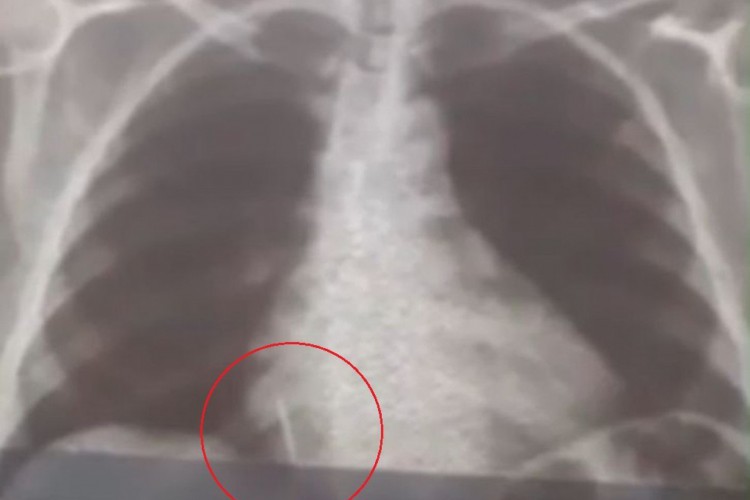

Há um mês, Iolanda Mariano de Melo aspirou uma broca durante a extração de um dente numa unidade hospitalar localizada no município de Lajes, no Rio Grande do Norte. Desde então, a mulher de 55 anos já perdeu aproximadamente 10 quilos e sente muitas dores, já que o material está alojado no pulmão.

O caso ocorreu no dia 26 de julho. Exames foram realizados em Natal para saber o posicionamento do material. Uma cirurgia chegou a ser marcada para 11 de agosto, mas, conforme informou a Secretaria Municipal de Saúde de Lajes, o procedimento foi adiado, pois um dos equipamentos necessários para o processo quebrou.